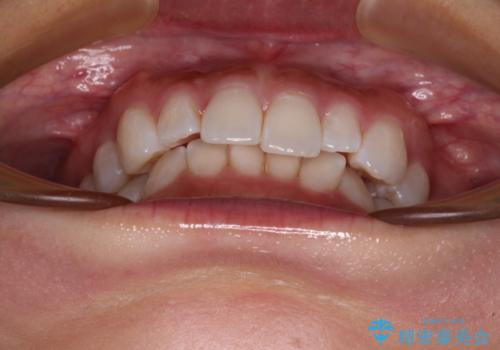

【モニター】前歯のデコボコと小さい前歯 インビザライン矯正とオールセラミッククラウン補綴治療

- 前歯の歯並びと生えてきたときから小さい前歯を気にして来院された患者様です。

上下前歯の歯列不正はインビザラインにより整え、その後に、矮小歯の前歯をオーダーメイドタイプのオールセラミッククラウンにて補綴治療することとしました。